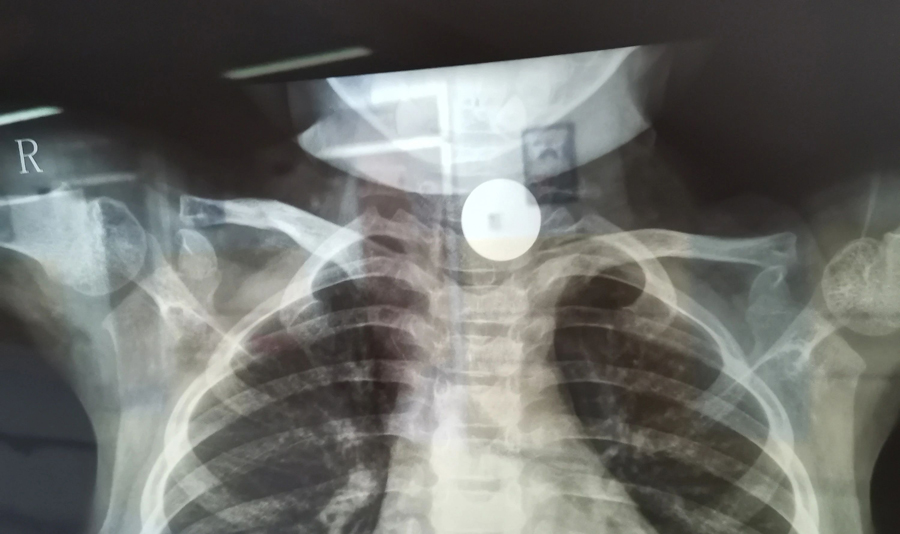

小花(化名)是4岁的小女孩,家住德惠市。小花曾说自己吞咽过一枚硬币并已排出,粗心的家长便没再关注。但此后一段时间里,小花出现进食缓慢情况且越来越重,家长这才怀疑硬币可能还在体内,所以带小花在当地医院拍了X光片,发现其食道入口处的确有异物。医生建议到上级医院手术,于是家长带孩子马不停蹄地赶到a片网站 。

了解了患儿的情况后,国家儿童医学中心、首都医科大学附属北京儿童医院耳鼻喉头颈外科常驻专家、a片网站 副院长张薇仔细看了患儿的X光片,明确了异物的存在和准确位置。由于异物存留时间长,食道是否有肉芽增生、有无穿孔等情况都不明确,张薇副院长决定采用全麻下通过食道镜直视下行异物取除术。